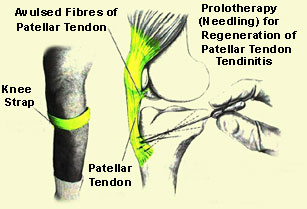

Tendonitis

Tendons are tissues which attach muscle to bones, when inflamed through injury or repetitive stress this is known as tendonitis. Key areas for a runner are knees and feet, one of the most painful being Achilles tendonitis

Patellar tendinitis of the knee can be treated moderately with the RICE method and in serious cases needle therapy to regenerate the tendon (ouch)